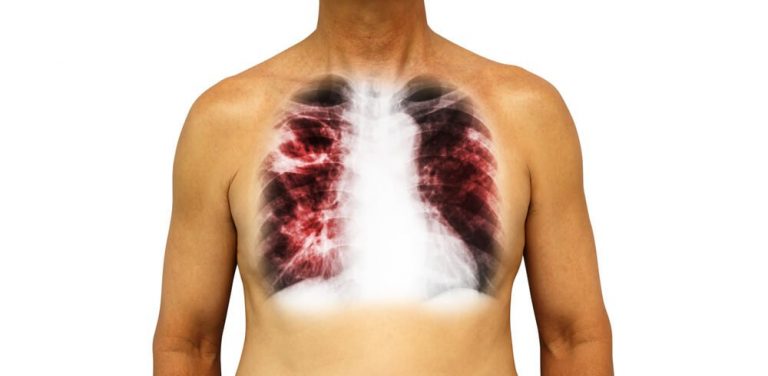

A tuberculose é uma doença infecciosa provocada pela Mycobacterium tuberculosis. Esta bactéria já foi bastante comum, tristemente famosa por se ter sagrado numa das principais causas de morte no mundo. No século passado, a epidemia foi responsável por mais de um quarto dos óbitos na Europa. Apesar da tuberculose ser considerada como uma doença controlada … Continue a ler Tuberculose – Formas multiresistentes